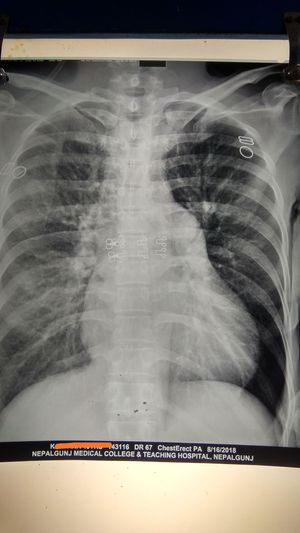

It is the case of Isolated TR. See left aorta hypertrophied, and left ventricle as well in Chest X-ray.

I think there's pneumothorax with collapsed lung on the left side, increased bronchial markings on right